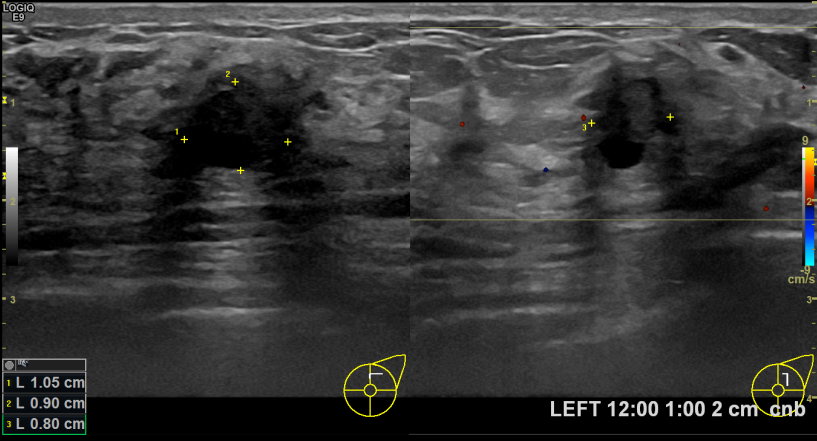

아산유외과개원후 730번째 유방암진단

상기환자 건진상 이상소견으로 조직검사권유받고 내원하신 60대 여성분으로 좌측유방멍울 조직검사시행후 유방암 진단되었습니다.